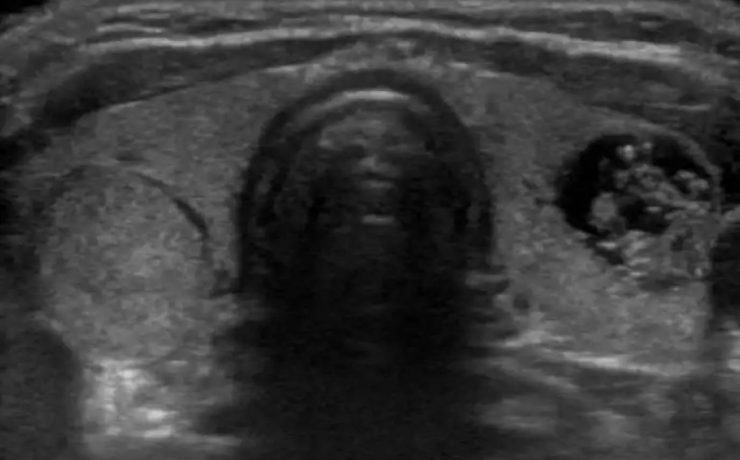

Signo radiológico: “el lirio caído”

El signo del lirio caído , fue descrito hace más de 40 años en pielografía de eliminación y corresponde al aspecto que adquiere el sistema pieloureteral inferior en un riñón con doble sistema excretor, dado por una pelvis renal de orientación horizontal y cálices que se dirigen discretamente hacia cauda.